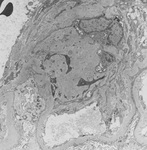

Doença renal diabética

Doença renal diabética: a expansão mesangial é geralmente reconhecida quando excede 1.5 vez a matriz mesangial normal

Do acervo do Dr. Raoul Fresco; usado com permissão